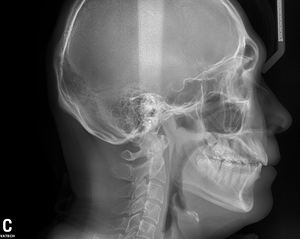

パノラマは大体どこの歯科医院にもあります。「セファロ」は顎顔面の状態をきちんと把握し、正しく治療を行う上で必要な横顔と正面から撮影したレントゲンです。

このセファロの撮影方法としては主に

デジタル方式の中でも最も少ない被ばく量の、ワンショットセファロを導入しました。今まで「最新」と言われていたデジタル方式では、アナログと比較して被ばく量が少ないものの、機種によって3秒から15秒近くの撮影時間が必要でした。その間、じっとしていないといけないわけですが、お子さんの場合は「じっとしていてね」といってもよけいに緊張して動いてしまう場合があり撮り直しすることがありました。

ワンショットタイプですと、撮影時間が0.5秒であっというまに終わります。

放射線を浴びる時間が0.5秒に短縮されます。

また、少し詳しい話になりますが、撮影した画像を感知するCCDというセンサーが従来品では顔の大きさより小さいため、縮小撮影してから大きく引き伸ばすため、画像が荒くなり細かい骨の状態が確認しづらいことがありました。当院で導入した京セラ製ワンショットセファロは、画像をそのままの大きさで撮影しますので、より

クリアーな画像で誤診を防ぎます。